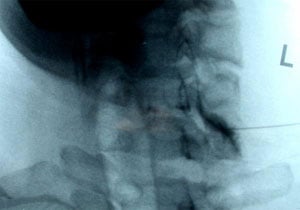

Figure 1: Model showing needle positioning for transforaminal epidural steroid injection.

Figure 2: Fluoroscopic image of a Left C6/7 transforaminal epidural injection. Contrast solution outlines the epidural space and exiting cervical nerve root. Immediately afterwards, a solution of corticosteroid and local anesthetic were injected.